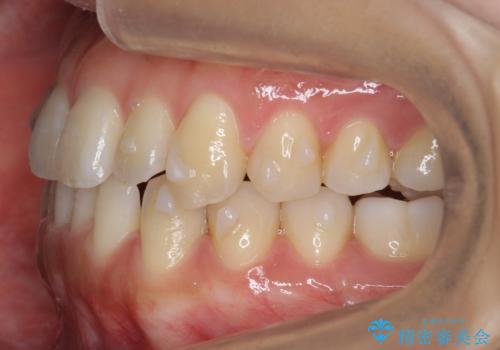

前歯のがたつき インビザラインで 下の奥歯を後ろに下げる

- 上下の前歯のがたつきを主訴に来院。

骨格的に受け口の傾向があり、下の奥歯が前方にに位置しており、下の前歯が特にがたつきが大きい状態でした。

下の奥歯を後ろに下げて下の前歯が前方に出ないように治療しました。

矯正用ミニスクリューを用いて治療しています。